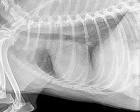

One important aspect of at-home care in left-sided congestive heart failure dogs is monitoring their respiratory rate, which is the number of breaths per minute. The respiratory rate can indicate the degree of fluid accumulation in the lungs and help determine if you need to see your veterinarian.

As a rule of thumb, a dog at rest should have a respiratory rate of less than 30 breaths per minute. Be sure to count in and out as one breath and be sure the dog is at rest or sleeping when you count. Do not try to count its respiratory rate immediately after physical activity.

Your veterinarian will also monitor periodic chest X-rays to assess the heart size as well as any evidence of fluid in the lungs. Blood work, including kidney values and electrolytes, will likely be recommended every three to six months to ensure your pet is tolerating their heart medication. The veterinary cardiologist will likely want to re-check an echocardiogram every six to 12 months to assess changes in the heart and make adjustments in medication as needed.